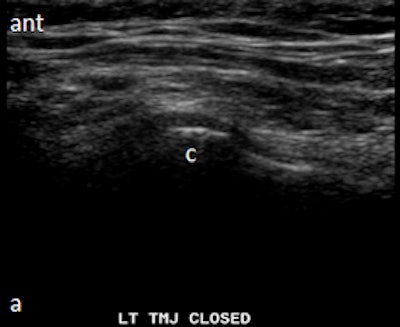

Dr. Friedman prefers that patients be supine on a stretcher with the jaw tilted away from the side to be examined. Then the person performing the ultrasound palpates the joint while the patient opens and closes her mouth. Gel is then placed on the joint, and the probe is placed at various positions around the joint. The images are examined to determine whether there is anterior displacement of the disk while the joint is the closed-mouth position.